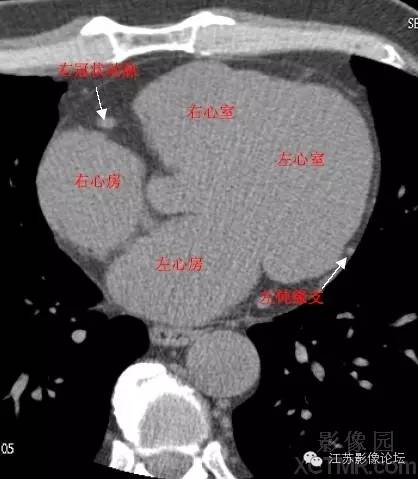

详细解读冠状动脉及冠心病ct

心脏ct断面解剖

带你全面了解心脏冠状动脉ct解剖

心脏解剖笔记:冠状动脉ct解剖及变异